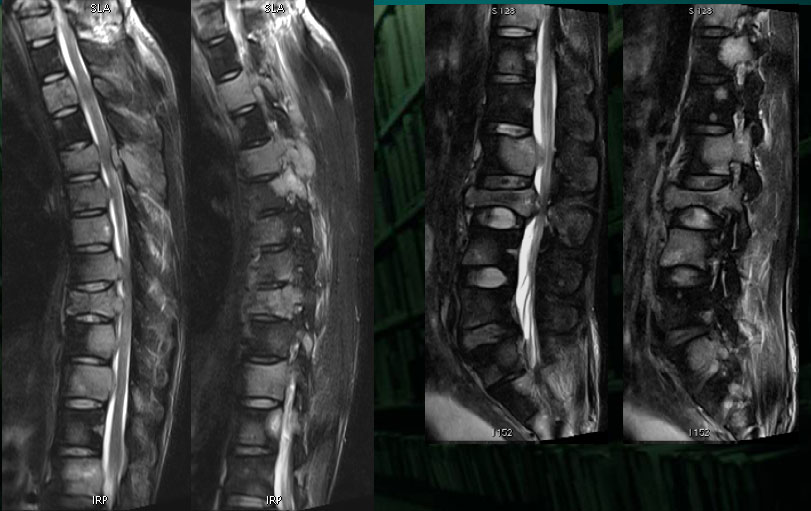

男性,20岁。

颈部疼痛2月,腰部臀部疼痛1月。

前臂肿物活检,病理报告:小圆细胞恶性肿瘤,免疫组化考虑为PNET/尤文氏肉瘤

In pPNET patients with tumors originating from soft tissues, the tumors often demonstrated ill-defined,soft tissue masses and exhibited aggressive spreading to the neighboring tissue.

On T1WI, the tumor demonstrated isointensity or slightly hypointensity; on T2WI, the tumor demonstrated heterogeneous hyperintensity.

The tumor demonstrated heterogeneous enhancement on contrast-enhanced CT/T1WI.

Cystic necrotic component and haemorrhagic change are usually obvious.